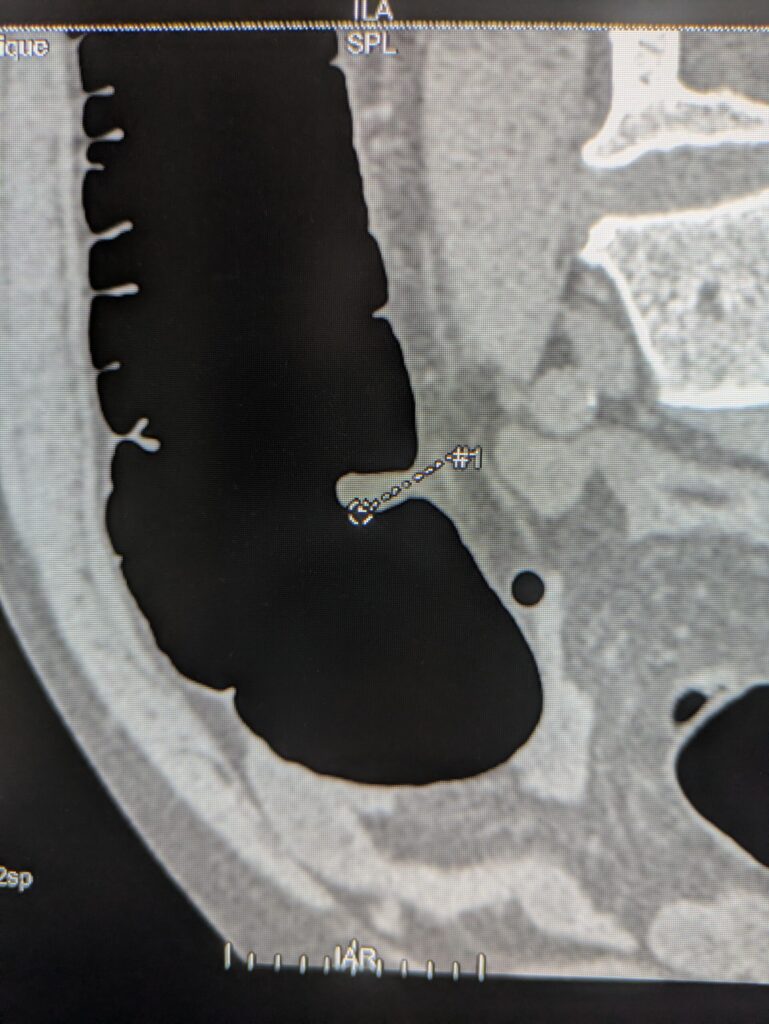

CTC uses CT scanning to create 3D images of the colon, allowing doctors to “virtually” inspect the inside without inserting a scope.

1. A soft tube is inserted about 4–5cm into the rectum.

2. Carbon dioxide gas (1,500–2,500ml) is introduced to inflate the colon.

3. CT scans are taken in supine and prone positions (10 seconds each).

4. 3D images and maps are generated with software.